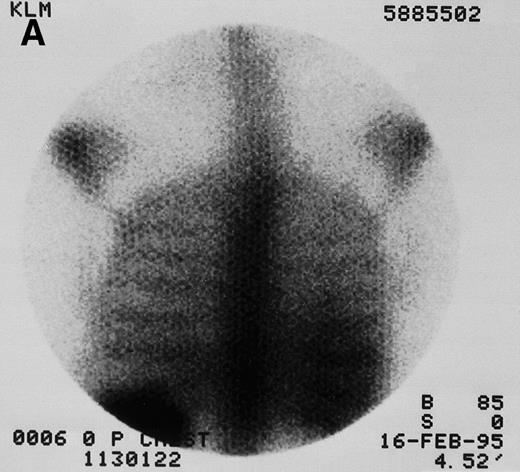

Quantitative gamma images were collected with a dedicated GE 400 AT large-field-of-view camera (General Electric Medical Systems, Milwaukee, WI) with a high energy collimator at hour 0 (end of infusion) and then daily for 2 to 3 days (Fig 1). Regions of interest (spleen, liver, lungs, kidneys if visible, and at least 2 marrow sites) were imaged using a 180° opposing view quantitative planar technique.40 Results were compared with an 131I imaging standard for quantitation and were corrected for whole-body thickness attenuation and radioactive decay. The time-activity curves for each source organ were integrated to obtain residence times. Because organ dose is roughly inversely proportional to mass, corrections were made for patient weight and organ mass when actual weights were known from CT or MRI. This correction was made by multiplying the observed source-organ residence time by the ratio of the defined reference man or woman organ mass to the known organ mass. Radiation absorbed doses were then estimated using methods consistent with those recommended by the Society of Nuclear Medicine’s special committee on Medical Internal Radiation Dose,41,42as previously described.43 The marrow clearance curve was scaled by correcting the biopsy-determined % ID/g of131I-BC8 by a multiplication factor of 2, because antibody cannot bind to the trabecular bone and fat that make up approximately half of the total biopsy weight.44,45 For dosimetry purposes, patient marrow volumes were normalized to the MIRD model values of 1,120 grams for an adult male and 1,050 grams for an adult female. For consistency, the same S values42 were used for all marrow dose calculations throughout the study. Statistical comparisons between disease type or stage and between anti-CD45 and control anti-iodiotype antibody used the Student’s t-test (SPSS for Windows 8.0; SPSS Inc, Chicago, IL).

131I-anti-CD45 antibody localization. Posterior 131I-BC8 images of patient with AML in relapse (UPN 9013) immediately after trace-labeled antibody infusion (A and C) and 40 hours after infusion (B and D). Accumulation of labeled antibody is shown in the ribs, vertebral column, ilium, pelvis, and sacrum, all marrow-rich regions of the axial skeleton.